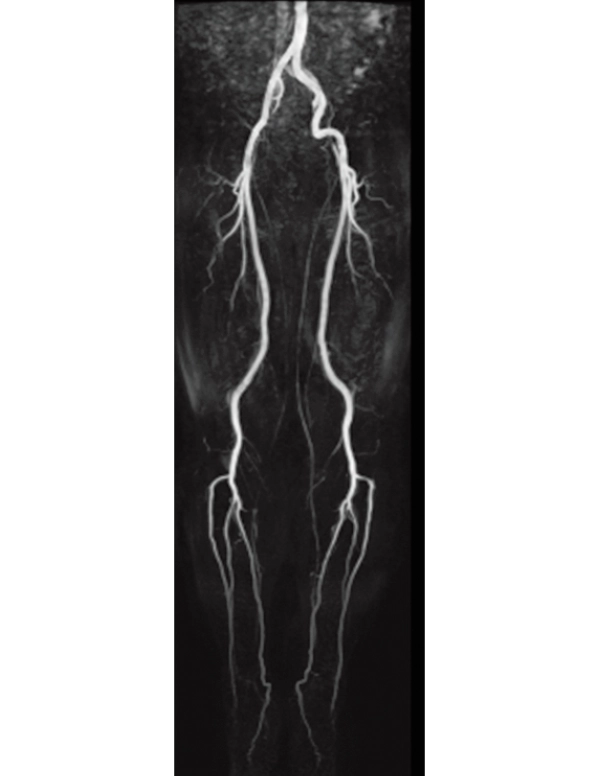

Lower extremity

non-contrast MRA (MIP)